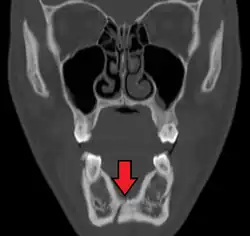

Nondisplaced fracture of the mandible

Plain film radiography

Traditionally, plain films of the mandible would be exposed but had lower sensitivity and specificity owing to overlap of structures. Views included AP (for parasymphsis), lateral oblique (body, ramus, angle, coronoid process) and Towne's (condyle) views. Condylar fractures can be especially difficult to identify, depending on the direction of condylar displacement or dislocation so multiple views of it are usually examined with two views at perpendicular angles.[11]